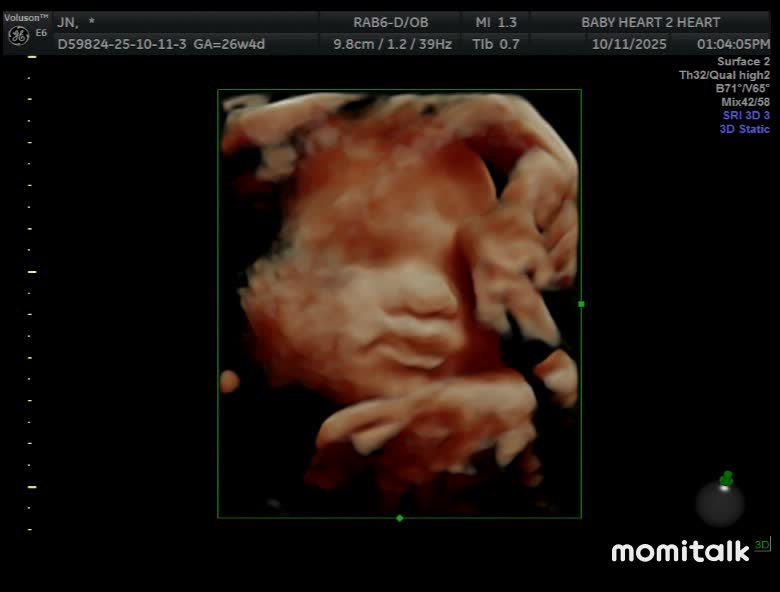

I can not wait to hold her ❤️